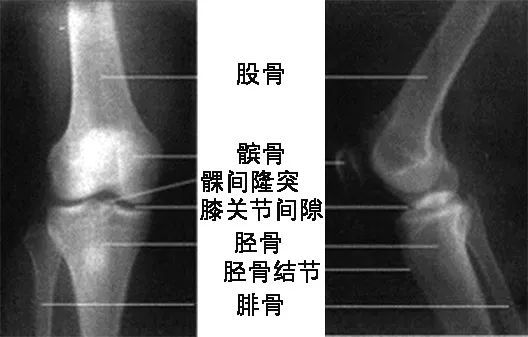

膝关节的解剖及功能_髌骨

膝关节由股骨内,外侧髁和胫骨内,外侧髁以及髌骨构成,是人体最大